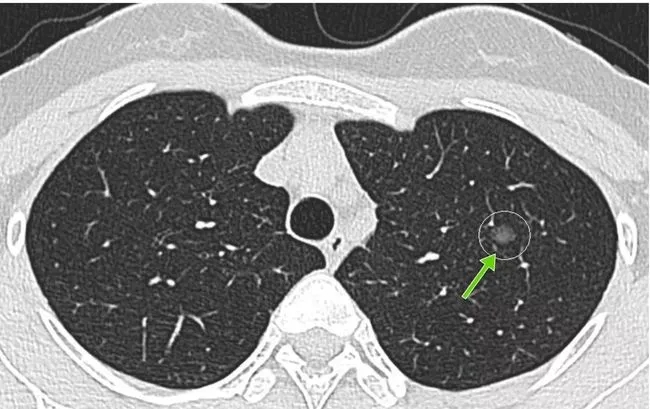

所謂的肺結(jié)節(jié),就是做胸部CT檢查時(shí)發(fā)現(xiàn)的肺部里密度增高的結(jié)節(jié)。

肺結(jié)節(jié)不是某種固定疾病的診斷,而是一個(gè)影像學(xué)上的定義。主要是指影像學(xué)表現(xiàn)為直徑≤3厘米的局灶性類圓形、密度增高的肺部陰影[1]。

(圖片來(lái)源于網(wǎng)絡(luò))